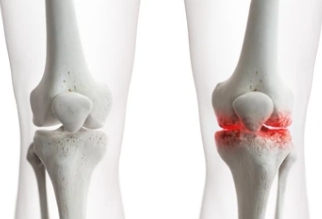

무릎은 대게 '관절염'과 연관이 있습니다. 퇴행성 관절염, 류머티스 관절염 등 관절염으로 인해 극심한 통증을 호소하고 거동이 불편하신 분들에게 시행합니다.